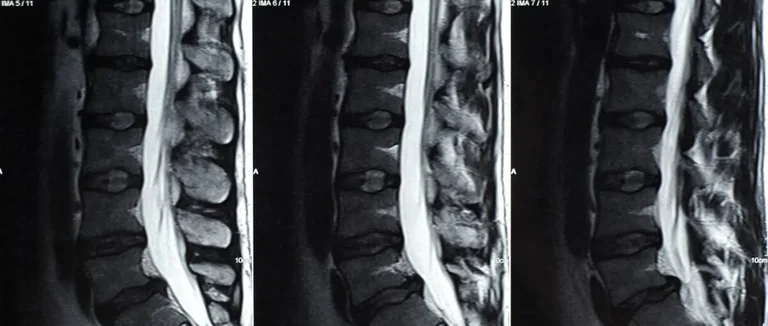

La colonne vertébrale est composée de vertèbres et de disques. Ces disques aident à amortir les mouvements et protègent la moelle épinière.

Anatomie de la colonne vertébrale

La colonne vertébrale est un système complexe. Il comprend les vertèbres, les disques, les nerfs et les ligaments. Les disques intervertébraux sont essentiels pour l'amortissement et la flexibilité.

Chaque disque a un noyau gélatineux entouré d'un anneau fibreux. Une hernie discale se produit quand le noyau sort par une déchirure. Cela peut causer des douleurs en compressant les nerfs.

Mécanisme de la hernie discale

Une hernie discale se produit quand le noyau gélatineux sort par une déchirure. Cela peut être dû à l'âge, une blessure ou l'usure. La hernie peut causer des douleurs et des faiblesses dans les membres.